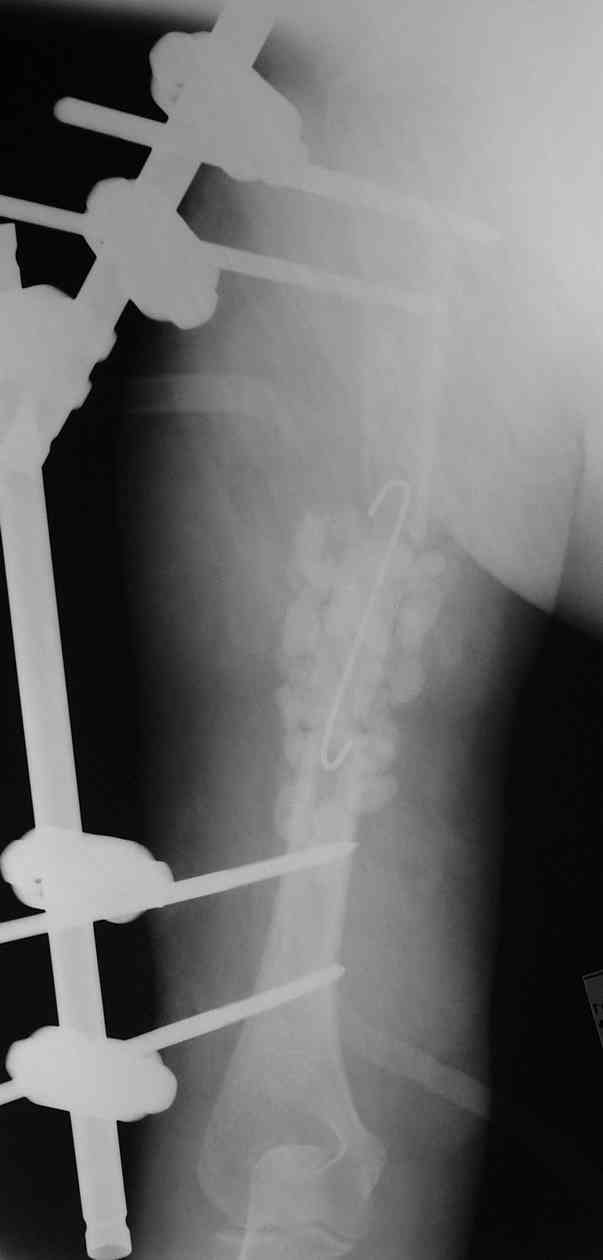

Через 2 недели интрамедуллярный остеосинтез с замещением дефекта кости цилиндрическим металлокаркасом (А.Ф. Лазарев подарил). Дренажи удалили, раны зажили, свищи закрылись. В конце августа благополучно выписана с движениями в локтевом суставе в объеме 0-10-100 град. в плечевом - отведение 45, сгибание -60 (стакан поднять могла).

27.11 в состоянии не прекращающегося после выписки опьянения получила закрытый надмыщелковый перелом плеча на уровне дистальных блокирующих винтов в результате адекватной травмы. Снимки прилагаются.

Коллеги, как бы Вы лечили такой перелом, не принимая во внимание социальный статус и "безграничные" материальные возможности пациентки. Жду советов, комментариев и критики. А.Семенистый.